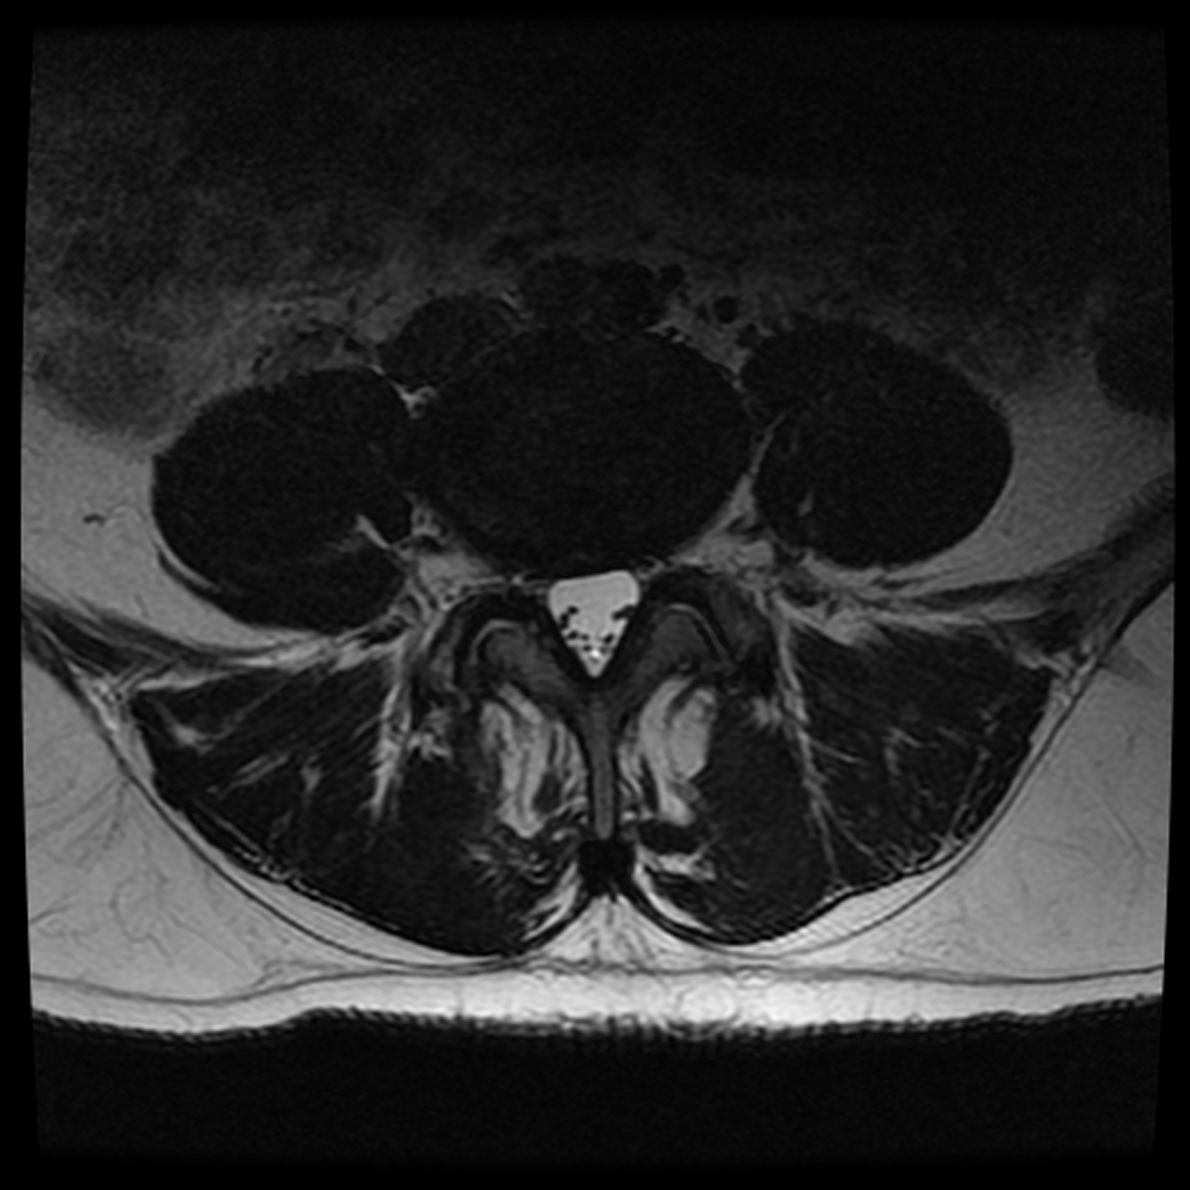

March 2019 MRI

IMPRESSION:

- Complete rupture proximal third anterior cruciate ligament with pivot shift

pattern of bone injuries lateral compartment and contrecoup bone contusion

medial tibial plateau. Joint hemarthrosis. - Complex tear lateral meniscus with inferiorly flipped flap tear extending

into the popliteal hiatus. - Complex tear medial meniscus with outwardly extruded tears of the posterior

horn and body. - Low-grade sprains medial collateral ligament and medial posterior oblique

ligament. - Low-grade sprains fibular collateral ligament and anterolateral ligament.

Intermediate to high-grade sprain popliteofibular ligament and arcuate ligament. - Grade 1 strains vastus lateralis, short head biceps, sartorius, soleus,

popliteus and anterior compartment muscles.